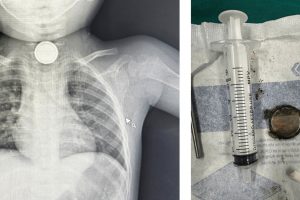

Cấp cứu trẻ nuốt cục pin của bộ điều khiển từ xa – Vừa qua, bệnh viện Nhi đồng Thành phố tiếp nhận một trường hợp trẻ Ph. T. Kh.. 21 tháng tuổi, nam, tạm...